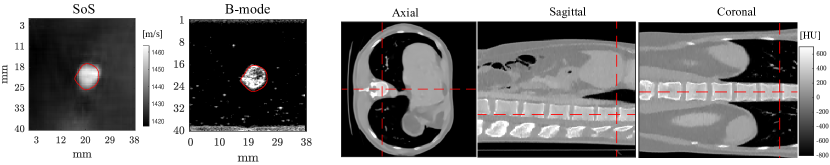

In Fig. 4 (a), we present a USCT SoS reconstruction from ex vivo bovine skeletal muscle tissue embedded in a gelatin phantom. Compared to the conventional B-Mode image, we could accurately identify inclusion location and provide quantitative estimates of local tissue SoS. Reconstruction of a single image with VN takes 0.03 s on NVIDIA Titan Xp GPU and 1-4 min with iterative methods on a 6-core 3.7 GHz Intel CPU. In order to demonstrate potential 3D imaging applications of our method, we also conducted X-ray CT reconstruction of SV-60 acquisition scenario with test images rotated by 90∘ in the axial plane, and show a cross-sectional views from the reconstructed 3D volume in Fig. 4 (b). We observe high spatial coherence and contrast in coronal and sagittal planes which asserts high generalization ability of the proposed expPC-VN method.

(a) (b)